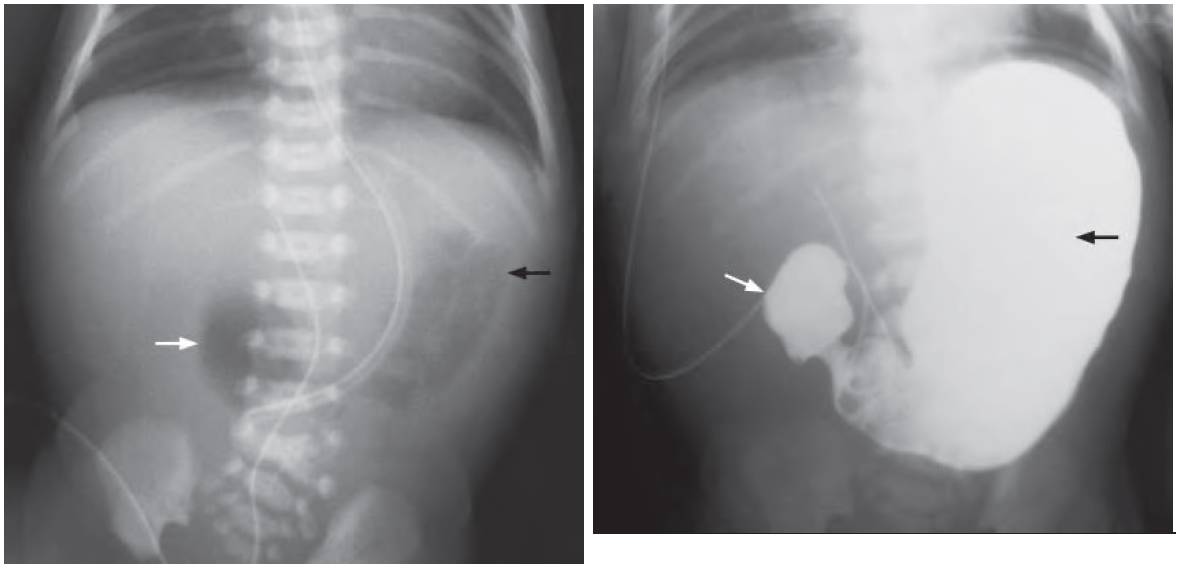

- ‘Double bubble’ sign due to the dilated stomach and the duodenum

- No bowel gas in the rest of the abdomen

Second image: Upper GI contrast study shows contrast opacification of the grossly distended stomach (black arrow) and the bulbousshaped duodenal cap (arrow). The rest of the duodenal loop and small bowel is not opacified, indicating complete obstruction and duodenal atresia. The diagnosis was confirmed at surgery.

- Double bubble sign is highly suggestive of duodenal obstruction.